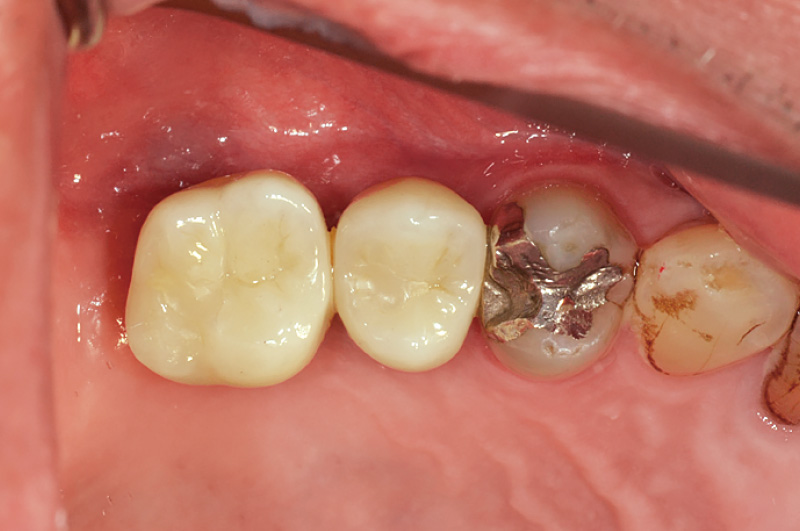

図1 症例① 術直前

術直前、浸潤麻酔後の写真を示す。#15, 16, 17歯欠損へのインプラント治療を希望された患者である。インプラント埋入に先立ち大学病院へ依頼してサイナスリフトを行った。八重洲歯科診療所における初めてSPIインプラントを用いて欠損部の修復治療を行った症例である。 -